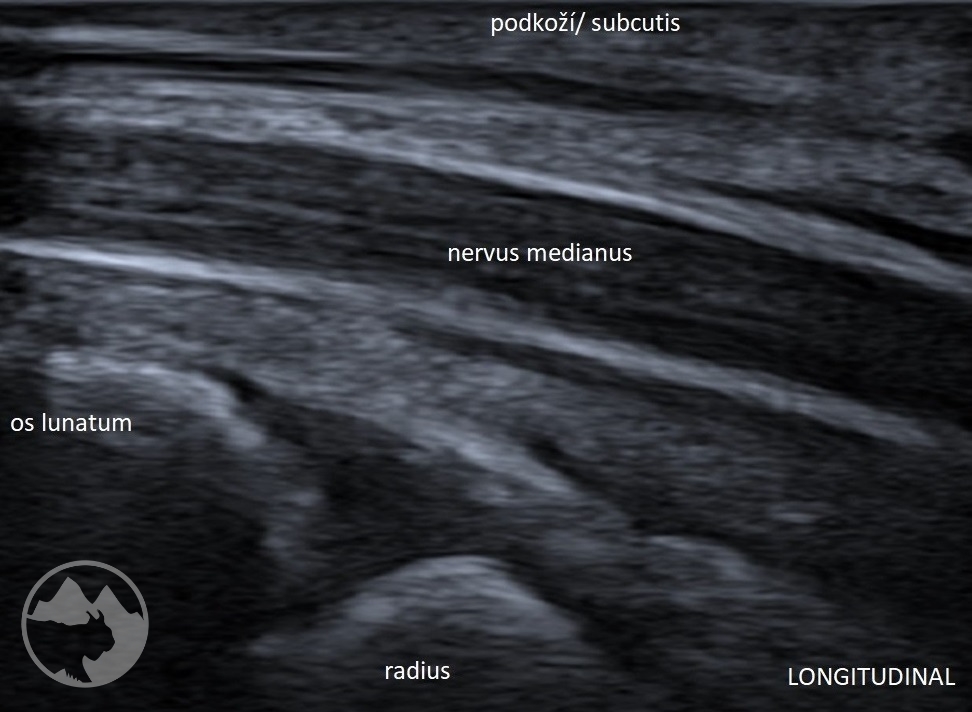

Workshop bude zaměřen nejen na samotné zobrazení daných nervů ve svém průběhu, nýbrž i na důležité topografické souvislosti s dalšími strukturami jako jsou kosti, svaly, cévy, vazy nebo fascie a na identifikaci anatomických „markerů“ a rizikových míst. V rámci několika přednášek budou zopakovány anatomické průběhy nejčastěji vyšetřovaných nervů včetně běžných variací, budou prezentovány možnosti měření, správného nastavení dopplerovského módu, ukázky úžinových syndromů a jiných patologických nálezů včetně důležitých „redflags“. Převažovat však budou praktické ukázky vyšetření a nácviky v malých skupinách. Vyšetřovací postupy zahrnou běžné statické zobrazení i skenování při pohybu, tzn. testy neurodynamiky. K dispozici na vyzkoušení budou standardní sondy i moderní vysokofrekvenční sondy s rozlišením umožňujícím hodnocení jednotlivých nervových fasciklů. Součástí přednášek ani praktických nácviků nebudou intervenční postupy.

– n. medianus